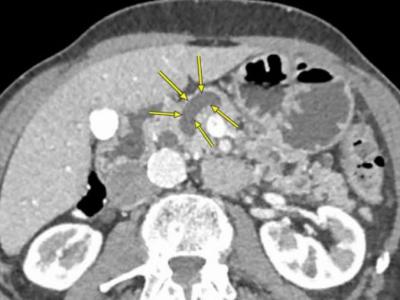

更早且更勤地切除某些胰腺囊肿可能会降低

更早且更勤地切除某些胰腺囊肿可能会降低某些患者患胰腺癌风险...